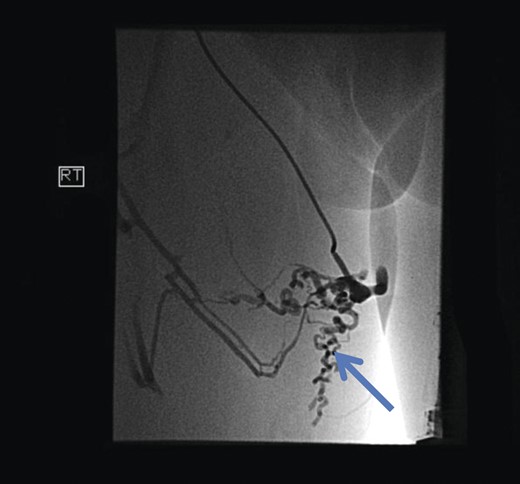

Initial investigations included duplex scan, followed by magnetic resonance scan. Duplex scanning demonstrated a competent sapheno-femoral (SFJ) and Sapheno-popliteal (SPJ) junctions bilaterally; however, did raise suspicion of a pelvic origin of the vulval varices with congested pelvic veins. Magnetic resonance venogram aided the diagnosis by demonstrating the communication of the vulval varices to the upper thigh veins with contribution from the internal iliac vein. In this case there was no evidence of ovarian varices (Fig. 1). Catheter venography was unable to confirm the contributing vein with certainty but computed pelvic venography showed a likely connection through the superficial external pudendal vein (Fig. 2).

Computed pelvic venography showing communication of thigh veins to vulval varices (blue arrow).